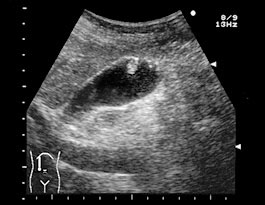

心エコー図は心臓の超音波画像です。

心エコー検査中、医師または技師が胸部上でトランスデューサーと呼ばれる装置を動かす間、人は動かずに横たわります。

トランスデューサは高周波音波を送信し、その結果生じるエコーを電気インパルスとして心エコー検査装置に送信します。

次に、エコー マシンは、検査のために電気インパルスを心臓の静止画と動画に変換します。

医師は心エコー図を使用して心臓の厚さと駆出率を評価します。駆出率とは、心臓が収縮中に送り出す血液の割合を指します。